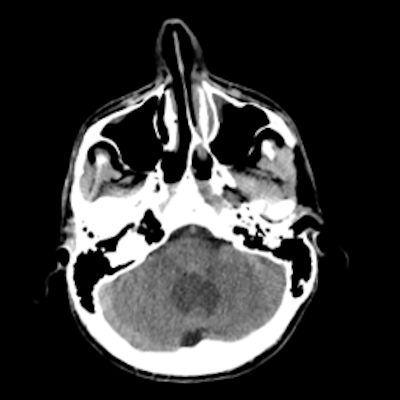

24 yaş, E

Baş ağrısı

4.ventrikül tabanına oturmuş posterior fossada hemanjioblastoma

Hemangioblastoma